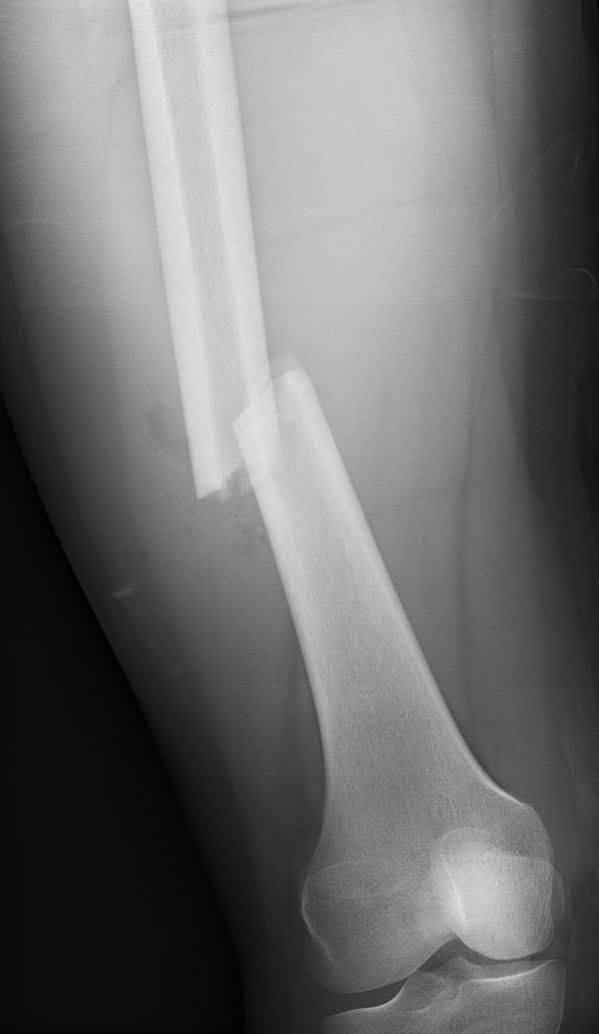

Omdat het dijbeen een zeer sterk bot is, komt een breuk hiervan meestal door een ongeluk waarbij er veel energie is vrijgekomen. Denk hierbij bijvoorbeeld aan een ongeval met een gemotoriseerd voertuig of een val van hoogte. Wanneer met de vorderende leeftijd de botten wat brozer worden (osteoporose), kan het dijbeen overigens wel makkelijker breken. De klachten van een gebroken dijbeen kenmerken zich door veel pijn in het bovenbeen met een onmogelijkheid het been te bewegen en te belasten. Vaak valt het ook op dat het been in een andere stand ligt. Een zwelling van het bovenbeen is niet altijd direct zichtbaar. Een Röntgenfoto kan de aanwezigheid en het beloop van de breuk aantonen.

Behalve een letsel van het bot is er ook vaak letsel van de zogeheten weke delen, zoals huid, pezen, spieren en eventueel zelfs vaten en zenuwen. Indien er sprake is van een ernstig letsel van de weke delen, kan dit leiden tot een open breuk (het bot komt dan in contact met buitenlucht) of zelfs uitval van de zenuwen en/of bloedvaten.